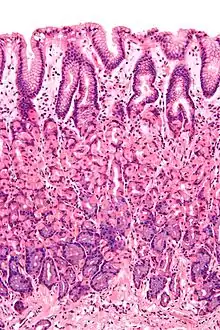

L'épithélium, la partie la plus exposée de la muqueuse, est un épithélium glandulaire avec de nombreuses cellules caliciformes. Les cellules caliciformes sécrètent du mucus lubrifiant qui facilite le passage des aliments et protège la paroi intestinale contre les enzymes digestives. Dans l’intestin grêle, les villosités sont des replis de la muqueuse qui augmentent la surface de l’intestin. Les villosités contiennent un canal chylifère, petit vaisseau connecté au système lymphatique qui aide à emporter lipides alimentaires et fluides tissulaires. Les microvillosités sont présentes sur l'épithélium d'une villosité et augmentent encore la surface par laquelle l'absorption peut avoir lieu. De nombreuses glandes intestinales sous forme d'invaginations en forme de poche sont présentes dans les tissus sous-jacents. Dans le gros intestin, les villosités sont absentes et une surface plane avec des milliers de glandes est observée. La lamina propria, qui contient les myofibroblastes, les vaisseaux sanguins, les nerfs et plusieurs types de cellules immunitaires, se trouve à la base de l'épithélium. La musculeuse muqueuse est une couche de muscles lisses qui favorise l'action du péristaltisme continu et de la catastase dans l'intestin.

- Dans l’estomac, l’épithélium est une monocouche de cellules en colonne et s’organise en fosses et glandes gastriques pour traiter la sécrétion[1]. Dans l’intestin grêle, l’épithélium est une simple monocouche colonne et spécialisé dans l’absorption. L'épithélium est organisé en villosités intestinales, créant une bordure en brosse qui augmentent fortement la surface d'absorption. Chaque cellule a aussi des microvillosités. L'épithélium est donc organisé en plicae circulares et villosités et, de plus, les entérocytes ont des microvillosités à leur surface apicale. Cela crée une bordure en brosse qui augmente considérablement la surface d'absorption. L'épithélium est une monocouche en colonne avec des microvillosités. Dans l'iléon, il y a parfois des plaques de Peyer dans la lamina propria. Les glandes de Brunner se trouvent dans le duodénum mais pas dans d'autres parties de l'intestin grêle[1].